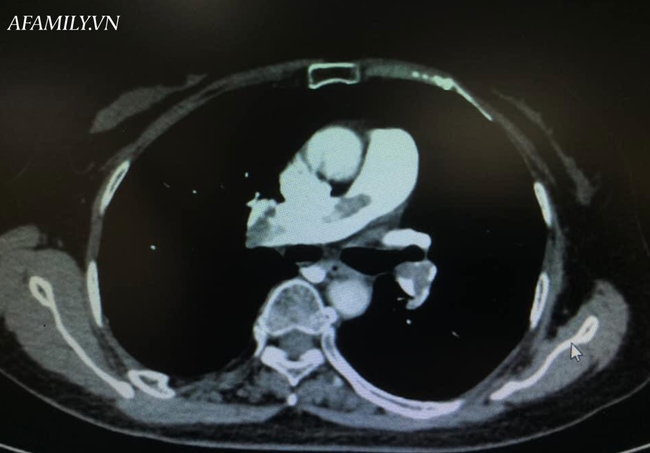

Bệnh nhân được tiếp tục truyền dịch, thêm vận mạch và được chụp CT khẩn động mạch phổi dưới sự hỗ trợ của khoa Chẩn đoán hình ảnh.

Kết quả chụp ghi nhận huyết khối động mạch phổi từ thân chung, 2 nhánh và các nhánh nhỏ.

Siêu âm cũng ghi nhận huyết khối tĩnh mạch sâu chân phải (bên gãy cổ xương đùi đang dùng nẹp chống xoay), thất phải dãn lớn trên siêu âm tim.